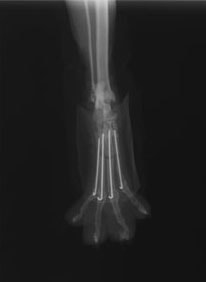

症例3:キルシュナーワイヤーのピンニングによる整復

ペルシャ猫 11ヶ月齢 雄

他院にて左大腿骨遠位の成長板骨折(salter-harrisⅠ型)が認められており、治療相談を目的として来院。当院にて、キルシュナーワイヤーを用いたピンニングにより骨折部位の整復を行いました。術後の経過は良好で、現在も経過観察中です。

術前レントゲン

術後レントゲン

機器

Arthrex社のターゲティングデバイスを用いてピンニングの位置を調整することで、確実な固定を行っています。当院ではこの手術器具以外にも、人の手術にも使用される様々な器具を導入し、手術精度を高め、また医療メーカーと新しい器具の開発、試作にも取り組んでおります。